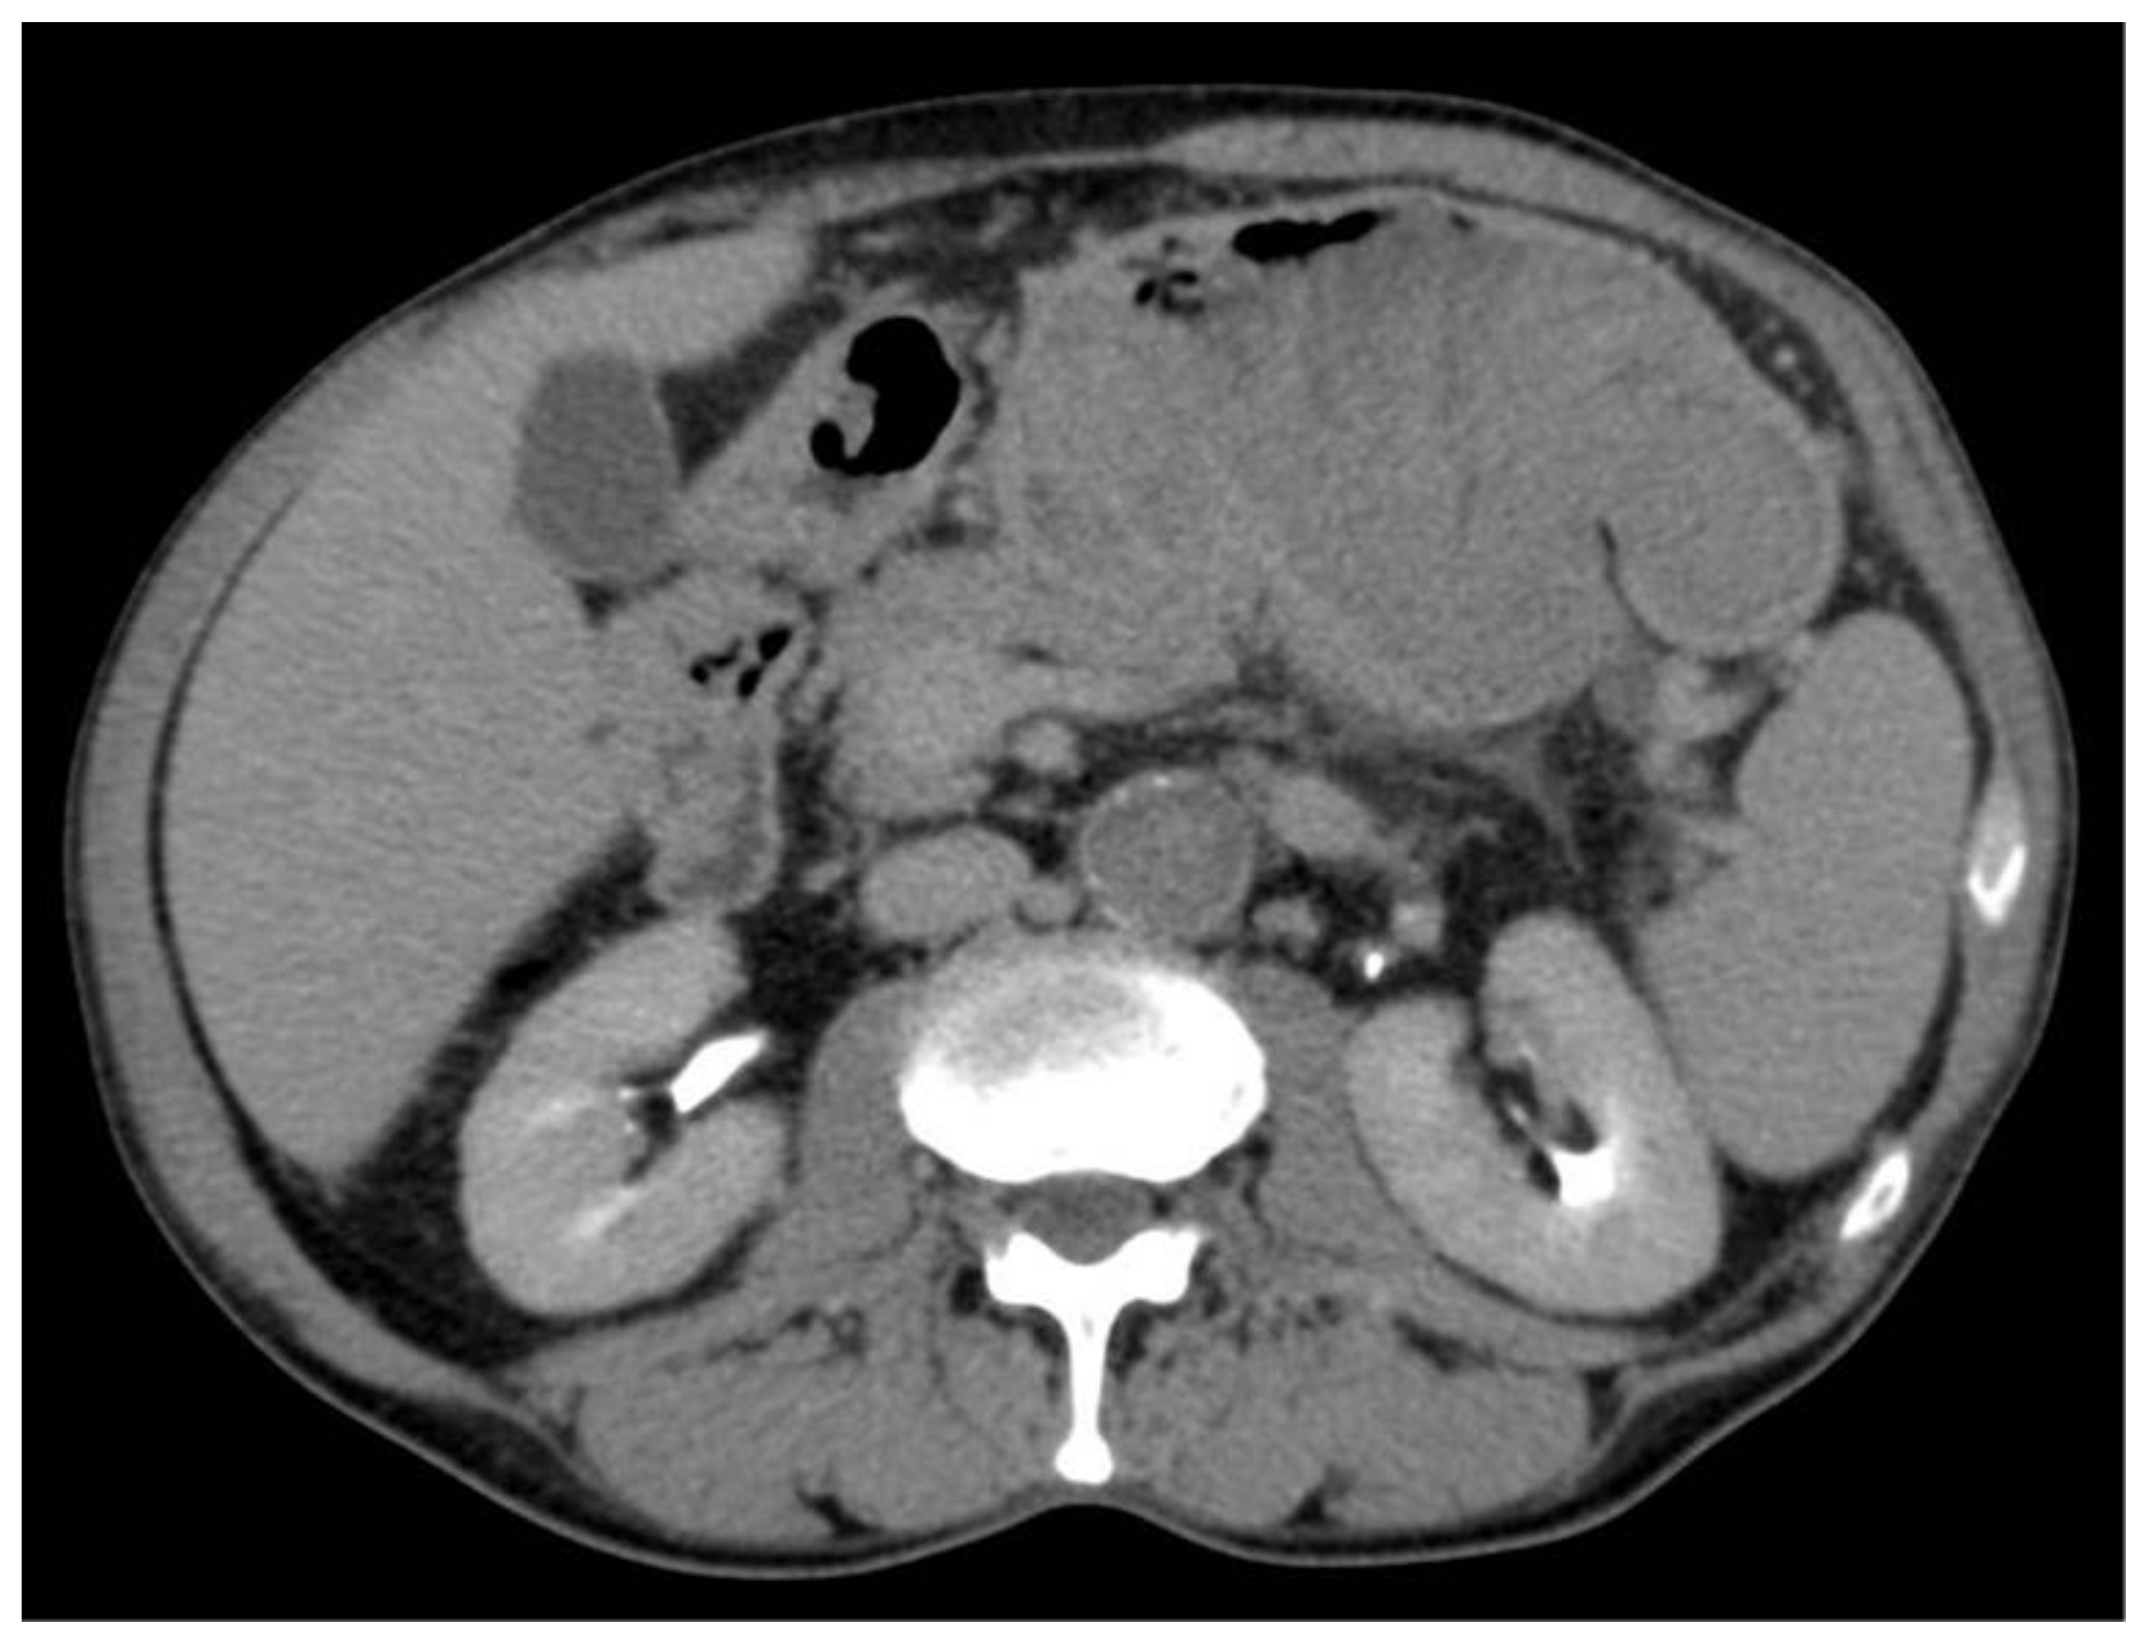

2. Case Report